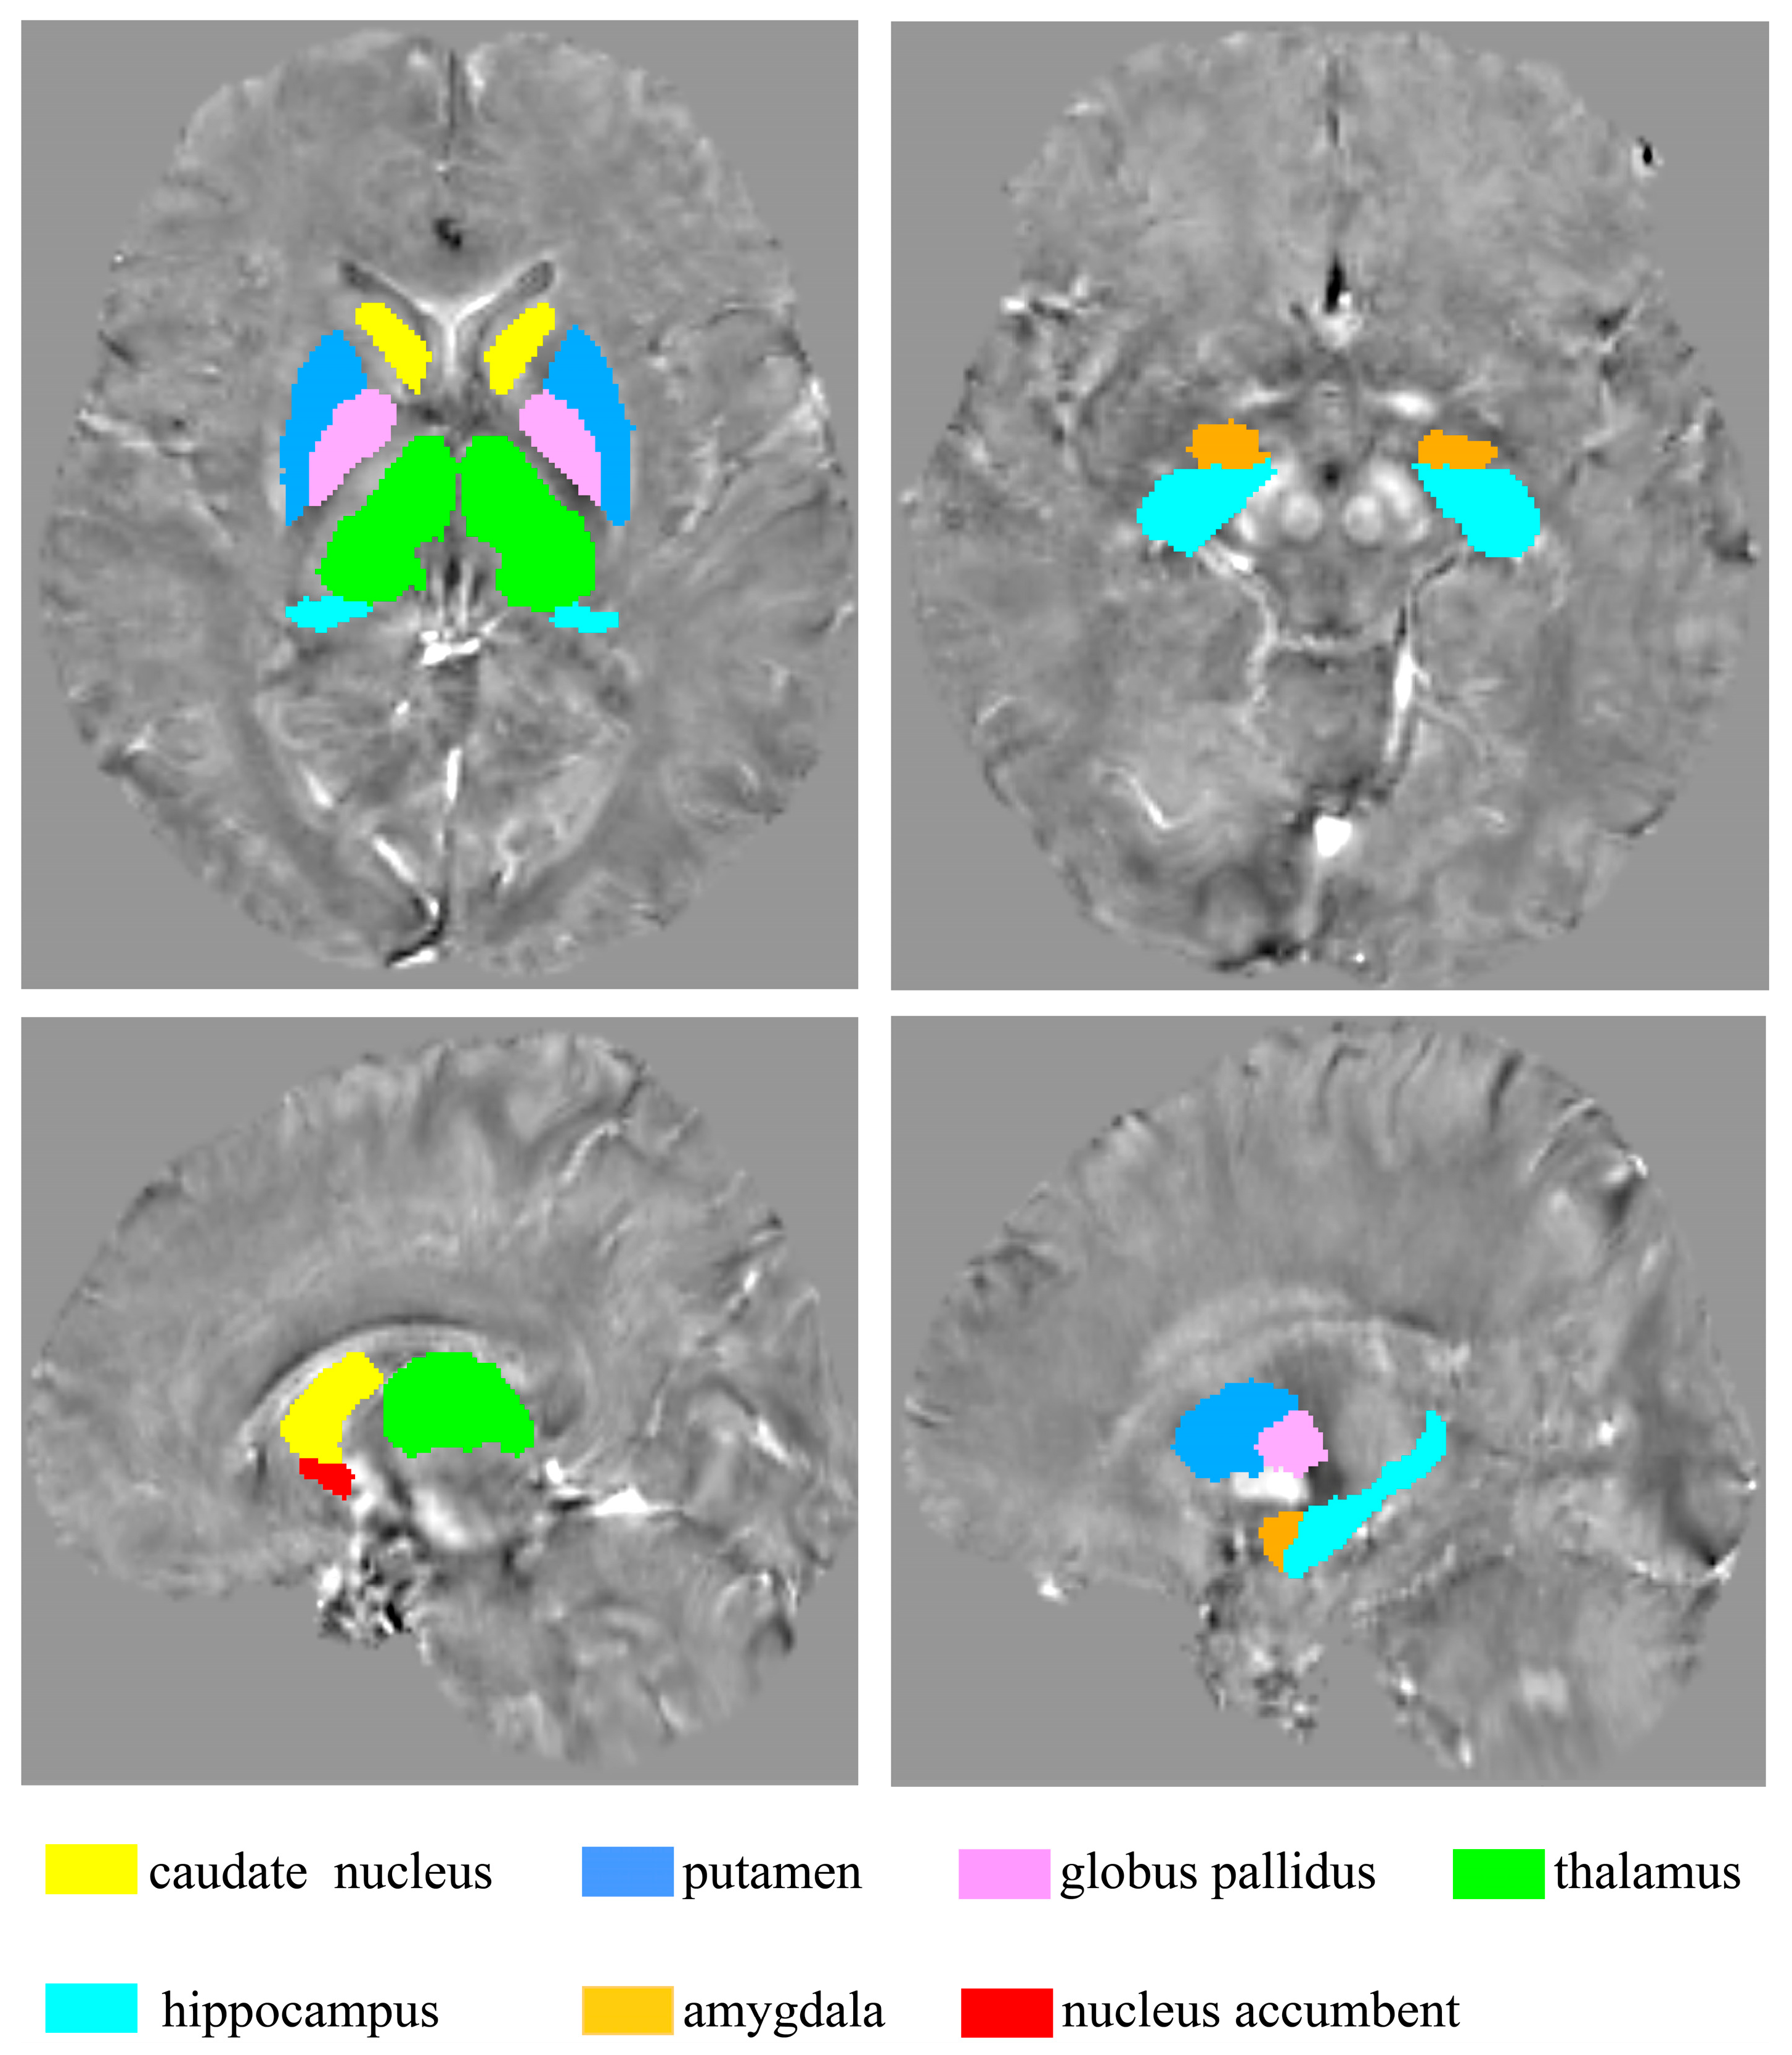

The ROI-based comparison of iron concentration in the brain between MDD and HC groups was conducted using fourteen ROIs delineated by the HOSubCort Atlas, as illustrated in Figure 5. This approach served to validate the results of the “MCCA+jICA” analysis.

Figure 5.

Fourteen ROIs were obtained according to the HOSubCort Atlas.

The ELISA results showed that MDD participants had increased pF content compared with HCs (Figure 6A) (*** p < 0.001). The mean and standard deviation of pF in the MDD and HC groups are 86.09 ± 4.10 ng/mL and 82.95 ± 4.30 ng/mL, respectively. Statistical analysis revealed that the QSM values in the right CN (* p = 0.039), left GP (** p = 0.007) and right GP (* p = 0.038) of patients with MDD were significantly lower than those in the HC group. On the contrary, in the left THA (* p = 0.028), the QSM values of MDD patients were higher than those of HCs (Figure 6B). The GMV values in the left THA (* p = 0.018) and left HIP (* p = 0.046) of MDD patients were lower than HCs (Figure 6C). Pearson’s correlation analysis showed that the pF contents were significantly positively correlated with the mean QSM values of left THA (r = 0.3039, ** p = 0.0036) (Figure 6D). However, in the left THA, no relationships were observed between GMV values and the pF contents (Figure 6E). Similarly, no significant correlation was found between the average QSM value and the average GMV value of the left THA (Figure 6F).

The comparison results of pF and ROI analysis of QSM and GMV values. (A) The pF levels in MDD patients were higher than those of HCs. (B) The mean QSM values in the right CN and bilateral GP of MDD patients were lower than those of HCs. However, the mean QSM values in the left THA of MDD patients were higher than those of HCs. (C) The mean GMV values in the left THA and left HIP of MDD patients were lower than HCs. (D) The pF contents were positively correlated with the mean QSM values of left THA. (E,F) No relationships were observed between GMV values of left THA and the pF contents. Similarly, no significant correlation was found between the average QSM value and the average GMV value of the left THA. QSM = quantitative susceptibility mapping; GMV = grey matter volume; MDD = major depressive disorder; HC = healthy control; CN = caudate nucleus; PU = putamen; GP = globus pallidus; THA = thalamus; HIP = hippocampus; AMY = amygdala; NAcc = nucleus accumbens.